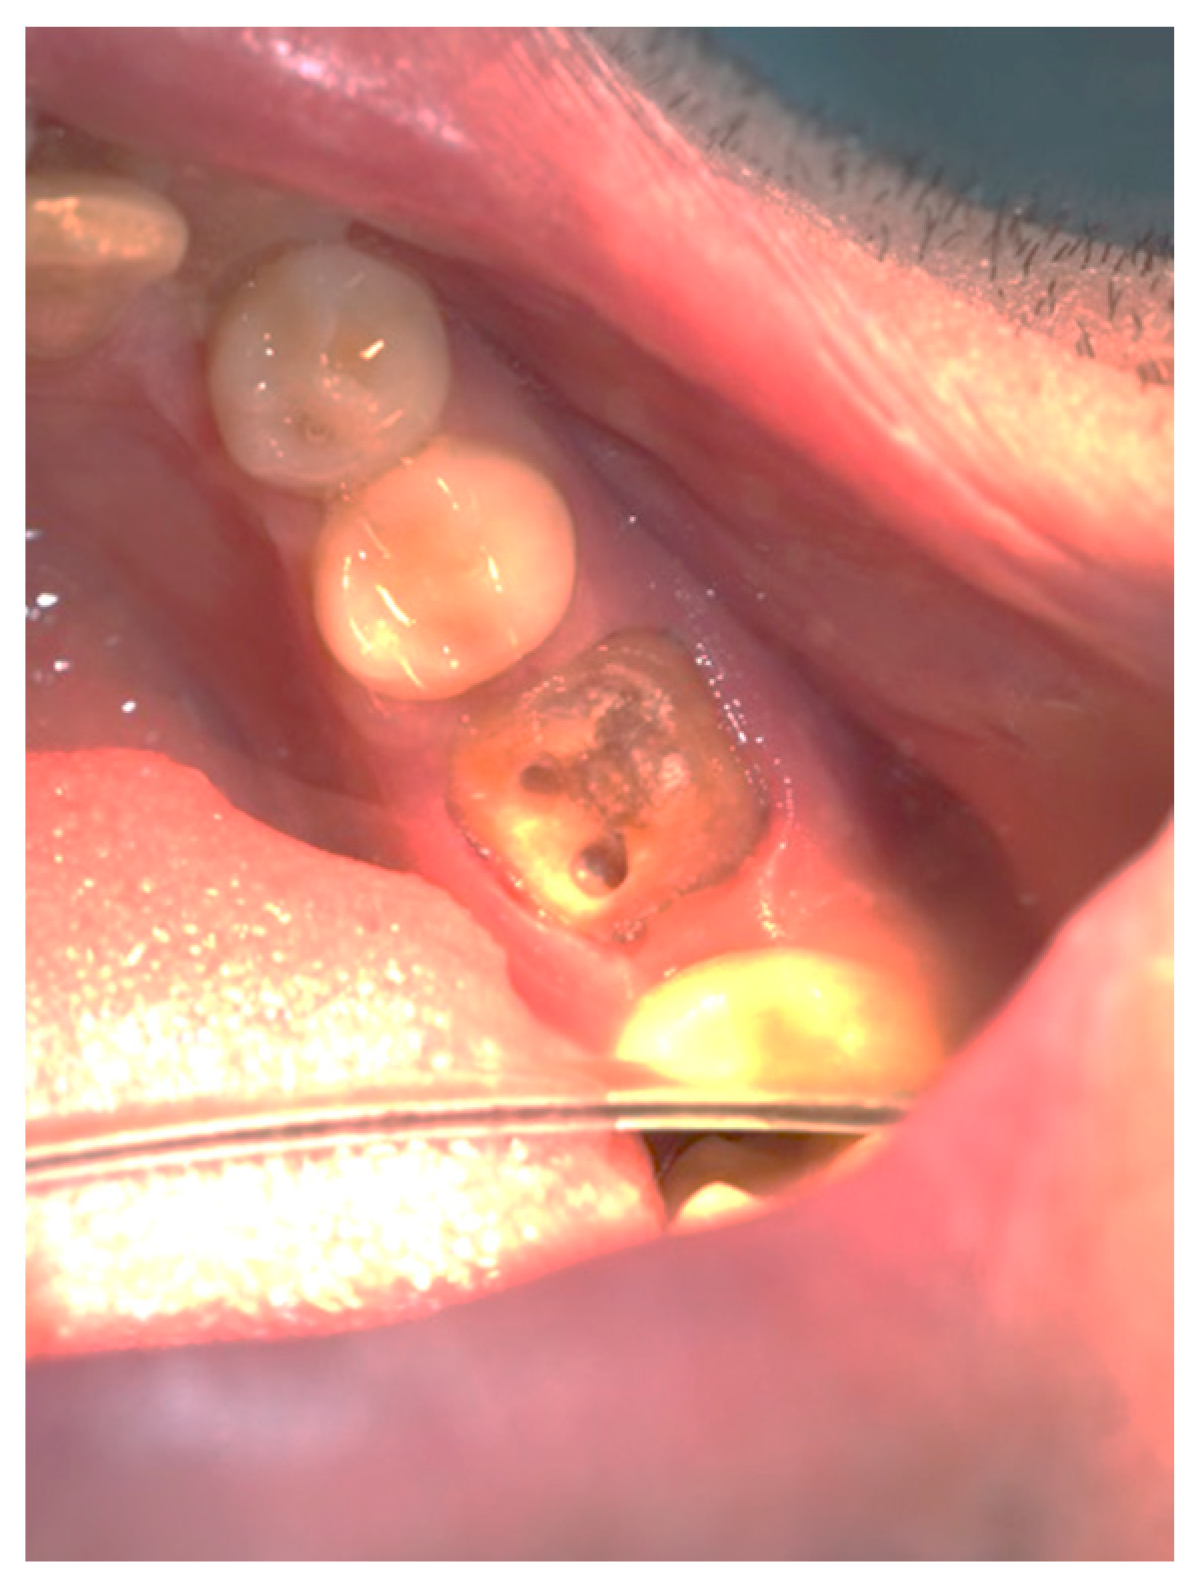

Figure 3, Figure 4, Figure 5, Figure 6, Figure 7 and Figure 8 display the follow-up of the healing process after a resective procedure for lengthening a short clinical crown with a laser.

Figure 6.

Healing in the 1st week: the wound was with a normal pale pink color, and the post and core was cemented.

Figure 7.

Healing in the 2nd week: the gingiva had a normal pale pink color.